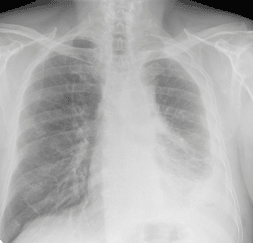

Chest X-ray of asbestos exposure

Mesothelioma

This is a rare type of cancer that arises in the membranes that surround certain organs. The majority of cases of mesothelioma are associated with significant asbestos exposure.

Lung cancer

Exposure to asbestos significantly increases the risk of lung cancer. There are many different risk factors for lung cancer, including smoking. However, asbestos exposure causes a ten-fold increase in the risk of lung cancer in nonsmokers. Those who are exposed to asbestos and who also smoke have 50 times the baseline lung cancer risk.

Asbestosis

This is a noncancerous disease in which scar tissue forms throughout the lung, which causes it to become stiff. This makes breathing difficult. The levels of asbestos exposure that can cause asbestosis are higher than those that can cause mesothelioma and lung cancer.